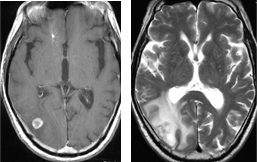

肺癌による左側頭葉転移性脳腫瘍に対してEGFR変異陽性の結果を踏まえて イレッサ(ゲファチニブ)の単独投与のみで治療したところ、腫瘍が著明に縮小しました。その後再発なく経過しています。

すべての症例でこのように効果が得られるわけではないので、薬物治療の恩恵が期待できない場合でも放射線治療が奏功する場合もあります。